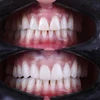

Zirkonyum uygulamalar

Porselen uygulamaları

Laminate veneer